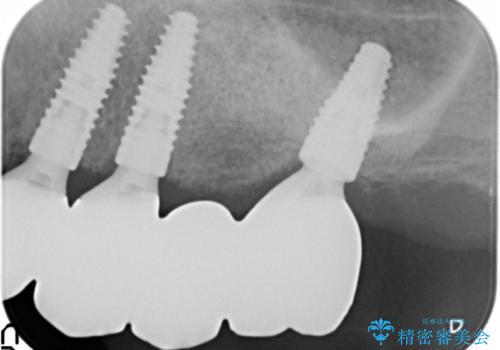

他院でインプラントできないと言われた 上顎洞底挙上術を併用したインプラント 50代男性

他院では上顎骨が薄いためインプラントできないと言われたとのことでした。

精査したところ、歯周病に罹患した歯を長年放置したことから骨吸収が進行し、上顎骨の厚みはとても薄くなっていました。

全顎的な歯周病治療を行ったのち、上顎洞底挙上術(上顎骨に骨を増やす手術)を併用したインプラント埋入を行いました。

インプラントの種類:ストローマン BLT